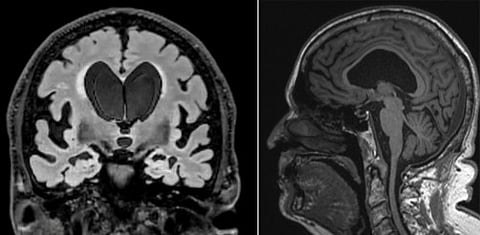

Based on his scans, the ventricles in the middle of Dick’s brain had enlarged a significant amount, likely caused by excess CSF and reduced outflow, which can disrupt communication between the brain and legs.

There also was evidence of disproportionately enlarged grooves in the brain, which happens when CSF is trapped in those spaces. On scans, this can look like brain shrinkage, which may have contributed to Dick’s earlier misdiagnosis.